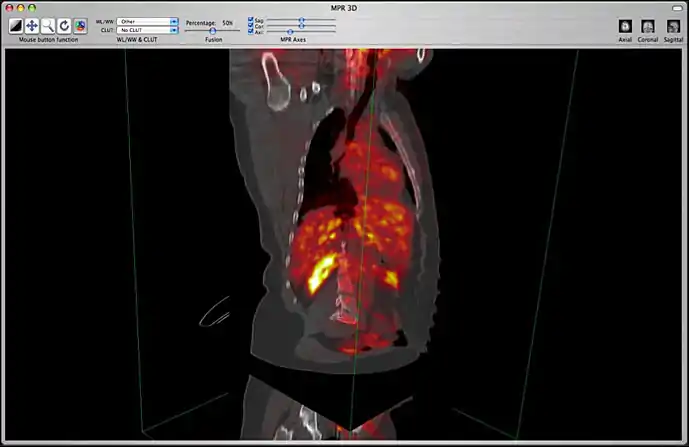

Image fusion is also available for 2D and 3D reconstructions implying that you can use image fusion along with MPR, Volume rendering, etc...

Image fusion in the 3D MPR window